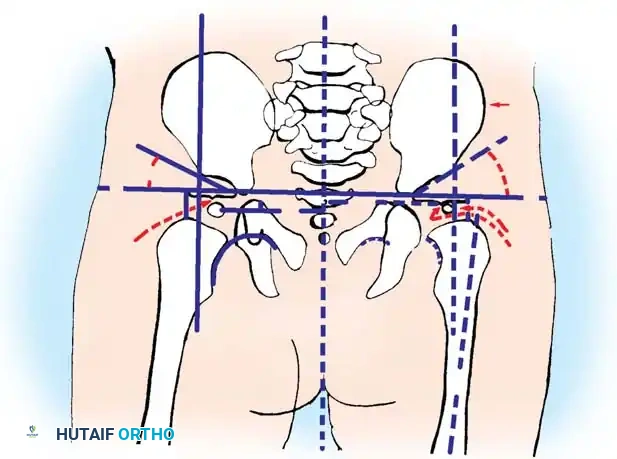

Radiography: Becomes reliable after 4 to 6 months as the ossific nucleus of the femoral head appears. Key radiographic parameters include:

* Hilgenreiner's Line: A horizontal line through the triradiate cartilages.

* Perkins' Line: A vertical line dropped from the lateral margin of the acetabulum, perpendicular to Hilgenreiner's line.

* Shenton's Line: A continuous arc drawn from the medial border of the femoral neck to the superior border of the obturator foramen. Disruption indicates proximal migration.

* Acetabular Index: The angle between Hilgenreiner's line and a line drawn from the triradiate cartilage to the lateral edge of the acetabulum. Normal is <30 degrees in newborns; >35 degrees is highly suspicious for dysplasia.

Radiographic evaluation: Normal hip anatomy (left) versus Dysplastic hip anatomy (right) demonstrating disruption of Shenton's line and an increased acetabular index.